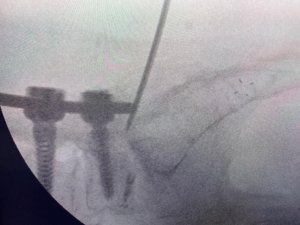

Türk Doktor, Bulduğu Yöntemle Literatüre Girdi